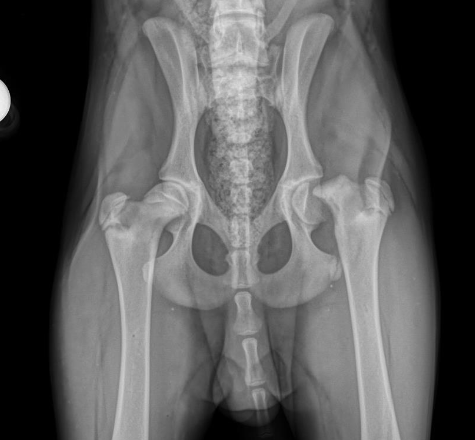

The most common radiographs made to evaluate dog hips are the traditional, “legs extended” view. These are also the type of radiographs that are reviewed by the Orthopedic Foundation for Animals (OFA) for grading. These radiographs are good, but imperfect. If these pelvic radiographs show a deformed hip, very loose hip, or an arthritic hip, one can confidently conclude that the dog hip is dysplastic. However, if the canine’s hips look good on these OFA radiographs, particularly in a puppy, there may still be laxity that just cannot be seen with these radiographs. That explains why OFA will not provide a grade on a dog’s hips prior to 2 years of age (unless the hips are obviously abnormal). This is due to the fact that these Orthopedic Foundation for Animals (OFA) style radiographs do not show hip looseness (laxity). As mentioned above, hip laxity is the first characteristic of hip dysplasia. Therefore, if the legs extended radiographs look very good, veterinary surgeons really want to know how lax (loose) the hips are. To know how loose the dog hips are, a veterinarian needs to take distraction radiographs.

Distraction radiographs, of which PennHIP radiographs are the most extensively studied and used, involve the physical distraction of the hips at the time of taking the X-ray to see how loose the dog hips are. From these PennHIP radiographs, the looseness is actually measured (called the distraction index; DI), not just subjectively estimated, and compared to the DI of many other dogs of only the same breed. With this information, a prediction is made as to the risk (ie probability) that your dog will develop hip osteoarthritis. These PennHIP distraction radiographs are most pertinent in assessing hips in young dogs that look good on the legs extended views. Knowing how loose those canine hips are, and the associated risk of developing osteoarthritis, can inform decisions on breeding that dog or on doing prophylactic surgeries to try and prevent the development of OA (see next).

OFA (left) and PennHIP (right) radiographs on the same canine patient. The hips look reasonable on the OFA images (left) but the extreme laxity is readily evident on the PennHIP radiographs.